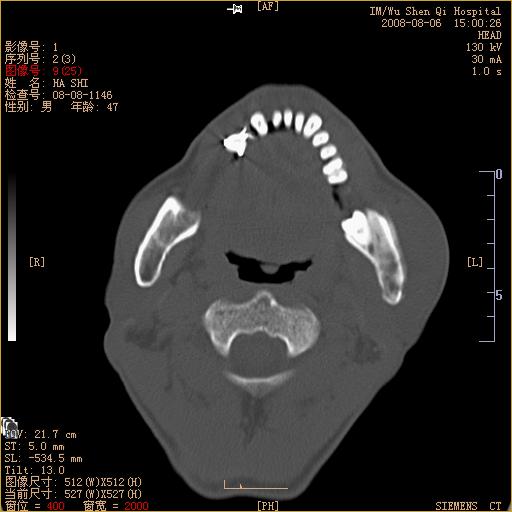

标题: CT15051:男 47岁 左下颌角部肿痛一周 [打印本页]

标题: CT15051:男 47岁 左下颌角部肿痛一周

骨质破坏,无硬化边,周围软组织肿胀,占位

左下颌骨感染性病变,牙源性可能。

左侧下颌智齿阻生。

考虑左下颌骨骨髓炎。